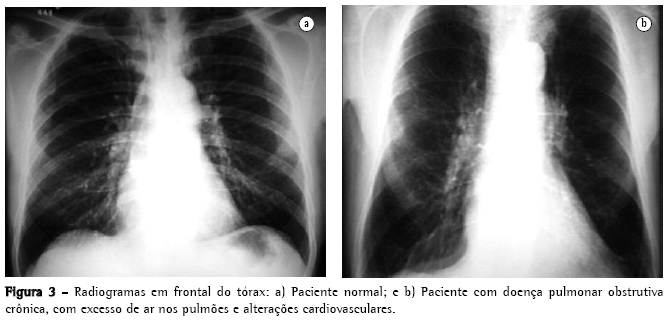

A correlação entre a anatomia patológica e a radiologia no estudo do enfisema é derivada do conceito de que o excesso de transparência no radiograma resulta de um aumento do volume de ar em relação à quantidade de tecidos pulmonares e sangue, que os feixes de raios X encontram em seu trajeto. Isto pode ocorrer quando o pulmão aumenta seu volume por expansão compensatória, desde que não haja um incremento significativo no fluxo sangüíneo, acompanhando o aumento de volume de ar. Entretanto, a redução do fluxo sangüíneo em determinada zona do pulmão pode ser a causa principal da redução da atenuação. Assim, bronquite e bronquiolite obliterantes podem ser responsáveis por aumento da radiotransparência, antes mesmo que a doença determine destruição das paredes dos alvéolos.

O rendimento do radiograma convencional de tórax na avaliação do enfisema é bastante limitado. Quando ainda não há aprisionamento aéreo significativo, a principal alteração é a redução da vasculatura, que somente é perceptível muito tardiamente na história natural da doença, e é um critério de extrema subjetividade. Quando há aprisionamento aéreo (Figuras 3 e 4), os critérios são mais seguros, podendo ser divididos em 3 grupos básicos de alterações,(6,8) apresentados na Quadro 1. Quando todos os critérios estão presentes, o diagnóstico é de certeza. Deve ser ressaltado que o aumento de câmaras direitas do coração, com redução da vasculatura intra-segmentar, pode também ser identificado em hipertensão arterial pulmonar, sem enfisema. Ressalta-se, também, que bolhas só estarão presentes em cerca de um terço dos casos.

Os objetivos do estudo radiológico de tórax, na avaliação do enfisema são o diagnóstico, a identificação do tipo lesional, e o julgamento da extensão da doença. Neste sentido, um estudo(6,8) traça considerações da mais alta importância:

Nos enfisemas de tipo centroacinar ou parasseptal, geralmente não há sintomatologia clínica, podendo haver aumento dos espaços aéreos, sem aprisionamento de ar nem alterações radiológicas evidentes; e

O enfisema panacinar, em geral, tem maior relevância do ponto de vista clínico, mas pode estar presente no pulmão do idoso, sem causar aprisionamento aéreo.

Alguns autores(15) relataram que o comprimento do pulmão direito e a altura do arco do hemidiafragma se correlacionavam bem com o VEF1 e a proporção VEF1/capacidade vital (CV). Neste estudo, um comprimento de pulmão direito de 30 cm ou mais identificou 70% dos pacientes com obstrução respiratória.(16) Entretanto, um autor(17) relata que todos esses estudos apresentam vícios, pois têm excesso de pacientes com obstrução respiratória crônica e, assim, as características radiológicas de obstrução aérea recebem "um valor desproporcional no reconhecimento do enfisema". Também foi demonstrado que a sensibilidade à radiografia de tórax não é boa, variando de 24(18) a 80%(19) e, também, que existe uma considerável variação intraobservadores e inter-observadores, em relação aos sinais radiológicos clássicos.(20) Os sinais radiológicos relacionados à vascularização estão sujeitos a uma variação intra ou inter-observadores ainda maior do que a dos sinais relacionados à hiperinsuflação.(19)

Um estudo comenta que o padrão enfisematoso definido pelo estudo radiológico convencional só está presente quando o enfisema é tão acentuado do ponto de vista anatomopatológico que, em geral, as reservas pulmonares já se exauriram ou estão no limite.(6,8) Uma revisão mais atualizada(22) reafirma essas proposições:

"Se os pulmões são levemente afetados por enfisema, o radiograma é freqüentemente normal";

"Enfisema pode ser diagnosticado pelo radiograma quando a doença é avançada"; e

"Somente metade dos pacientes com enfisema de extensão moderada são diagnosticáveis por radiograma de tórax."

Ambos os autores sugerem que o radiograma convencional de tórax não é um método confiável para o diagnóstico ou quantificação do enfisema.(22) Esta limitação é tão importante que alguns autores(21) demonstraram que, quando a radiologia convencional pode ser diagnóstica para doença pulmonar obstrutiva crônica, 53% dos pacientes estavam mortos em 5 anos e 70%, em 10 anos.